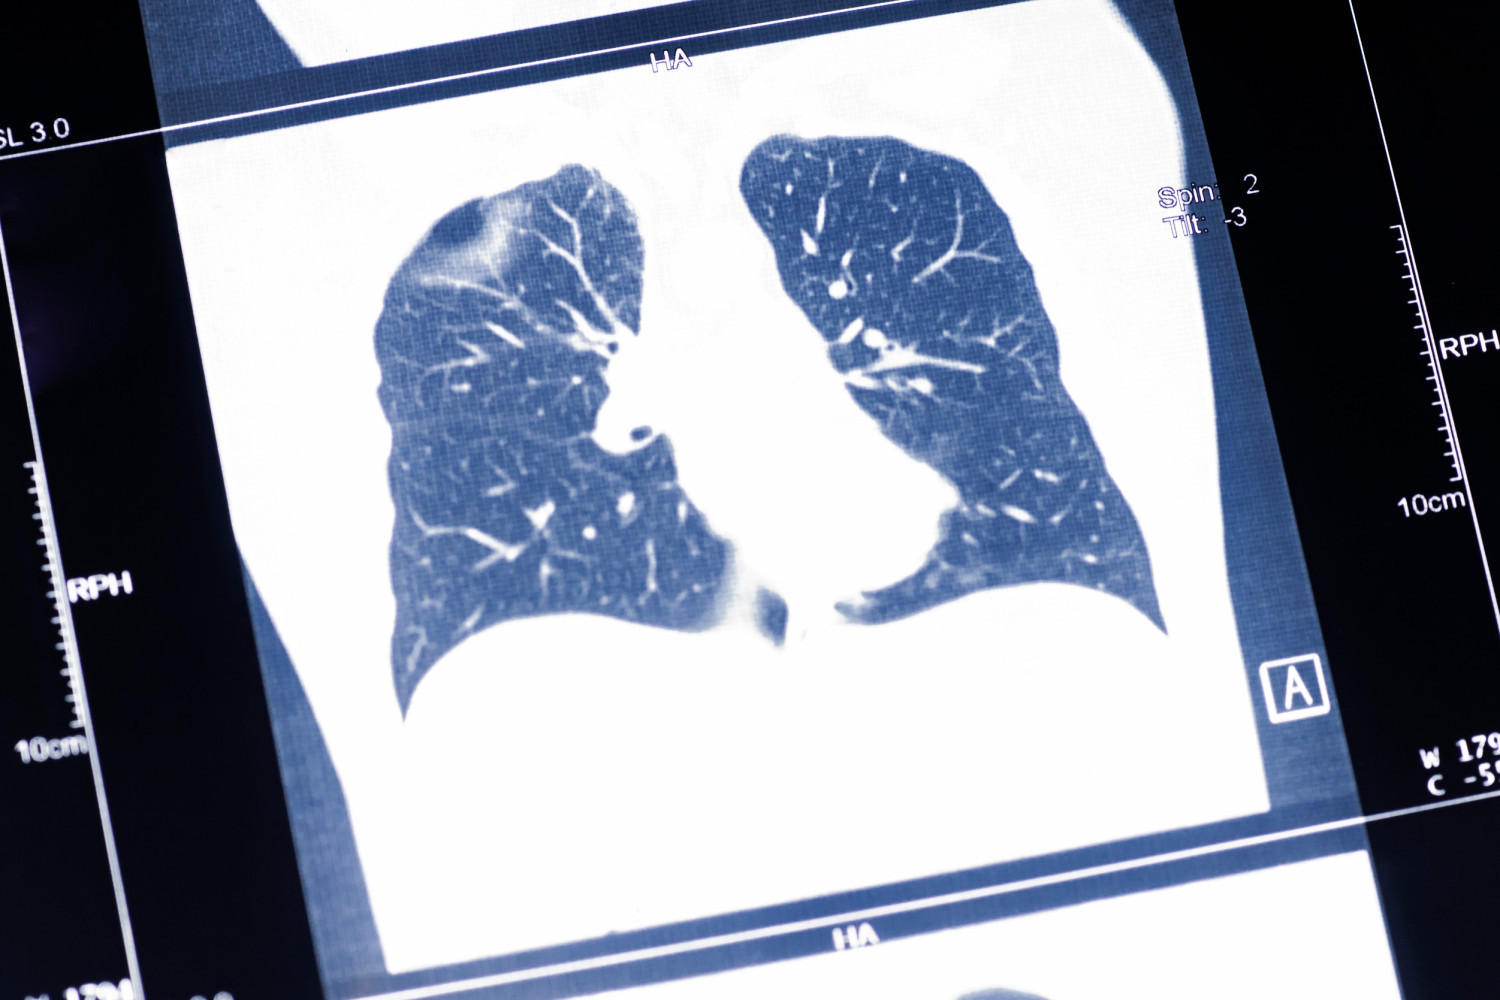

По словам эксперта, одна из наиболее значимых проблем современного здравоохранения в России и во всем мире — рак легкого. Он занимает лидирующие позиции среди всех онкозаболеваний по смертности. «Во многом это связано с низкой выявляемостью на ранних стадиях его развития, — объяснил Денис Романов. — Так, по данным ФГБУ «НМИЦ радиологии» Минздрава России, в стране около 70% случаев рака легкого диагностируются на поздних стадиях. В частности, речь идет о третьей и четвертой стадиях, когда возможности эффективного лечения уже существенно ограничены».